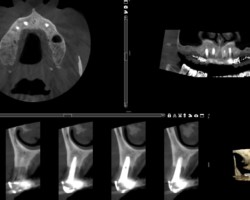

Avant-Après :